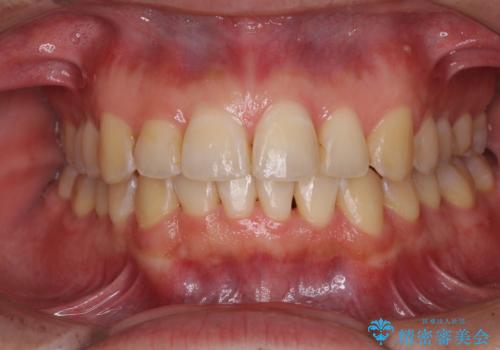

上下前歯の叢生をインビザラインできれいに

担当医 藤巻太一朗